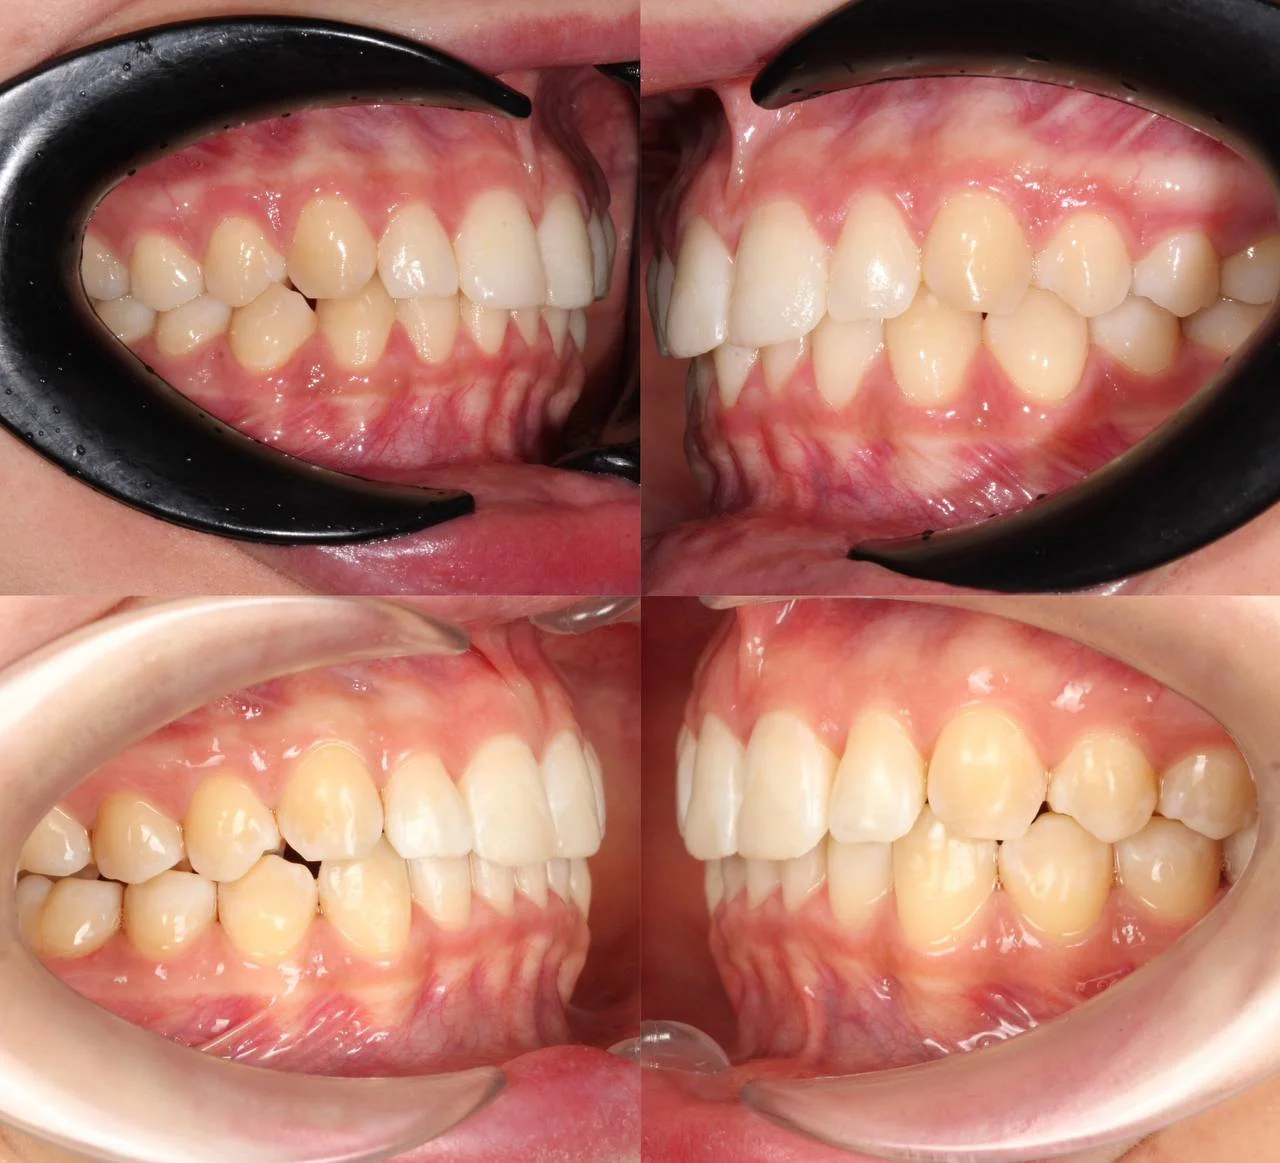

Прозрачные элайнеры Click на обе челюсти. Расширить зубные дуги, убрать скученность, выровнять линию смыкания. Основной набор — 32 капы. Срок — около 2 лет.

Лечение заняло 30 месяцев (август 2023 — февраль 2026). Понадобились три дополнительных набора: 30, 10 и 10 кап — итого 82 капы. Пациентка живёт за рубежом, приезжала на визиты — что иногда влияло на частоту контроля и сроки. На ретенцию приехала отдельно.

Решение: Поставили элайнеры Click на обе челюсти. Начали с 32 кап, но случай потребовал три дозаказа: 30, 10 и 10 кап — итого 82 капы за 30 месяцев. Количество дозаказов объясняется и сложностью случая (скученность плюс деформация кривой Шпее), и тем, что контрольные визиты были реже обычного из-за проживания за границей. Тем не менее результат достигнут: зубы ровные, смыкание в норме. На ретенцию пациентка приехала отдельно — зафиксировали ретейнеры на обе челюсти, сняли слепки для ретенционных кап.